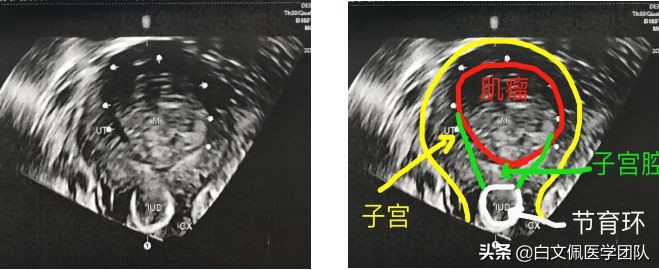

四、黏膜下肌瘤影响子宫腔形态,节育器下移,月经量过多,贫血

黏膜下肌瘤影响子宫腔形态,节育器下移,月经量过多,贫血。